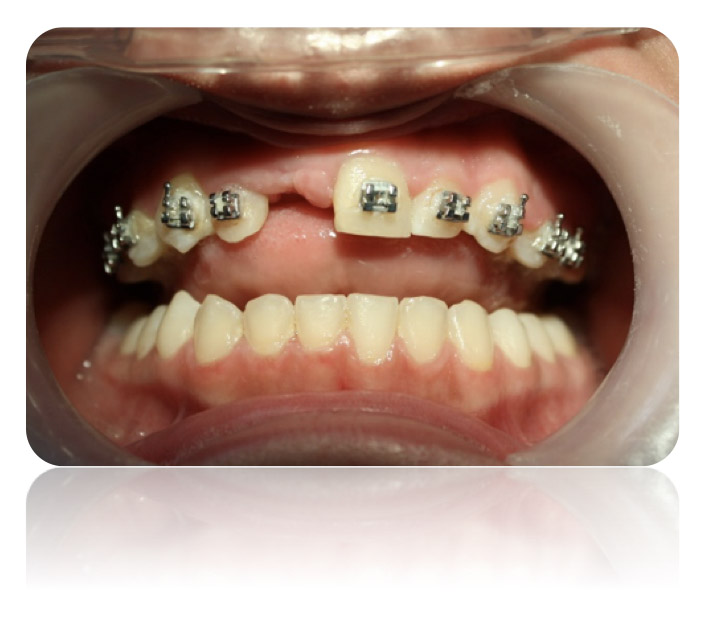

Los implantes son elementos metálicos usualmente en titanio puro que se ubican quirúrgicamente en los huesos maxilares, debajo de las encías. Una vez colocados en el lugar se puede colocar sobre ellos las coronas o puentes fijos que reemplazarán a las piezas dentarias perdidas